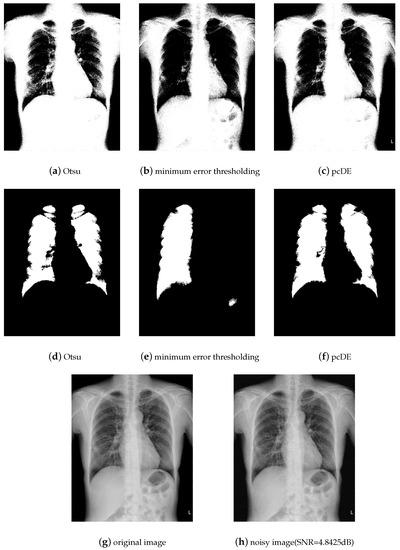

5. Case of Study: Parallel Compact Differential Evolution for Image Segmentation

- Image preprocessing. Enhance the contrast of the image to achieve better segmentation.

- Calculate the optimal threshold for image segmentation through different methods to get the binarized image.

- Use morphological methods to process images to extract targets.

- Mark target contour.

- : Represent the result of ground truth segmentation (Figure 13).

- : Represent the result of algorithm segmentation.

| Segmentation Method | Original Image | Noisy Image |

|---|---|---|

| Otsu | 0.9210 | 0.9531 |

| minimum error thresholding | 0.9732 | 0.9093 |

| pcDE | 0.9738 | 0.9684 |